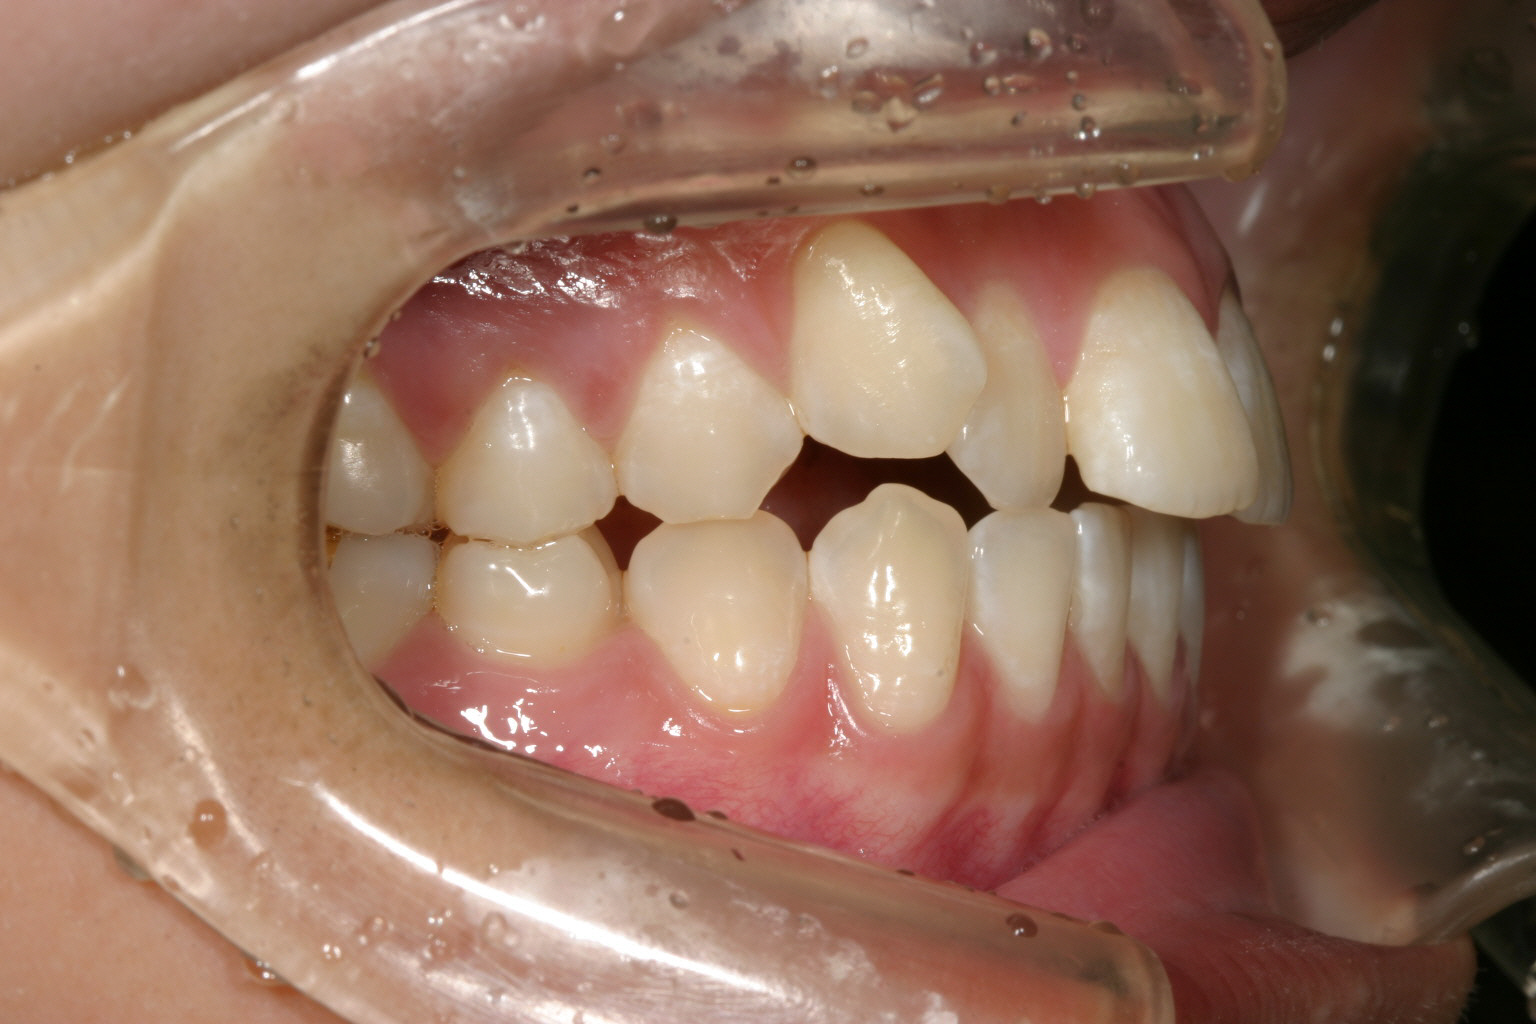

右の犬歯の突出が気になりますね~ 口の中を見ると単に糸切り歯が出てるだけなんだから入れればいいと簡単に考えるのですが 犬歯が並ばないのは奥歯が全体的に前に来ている為に犬歯の入るスペースが無く外に飛び出しているんです。 その為部分ワイヤーを用いて犬歯以後の臼歯を全体的に遠心移動(後ろに送る事)しました。

犬歯が飛び出して奥歯が上手く噛めていません。